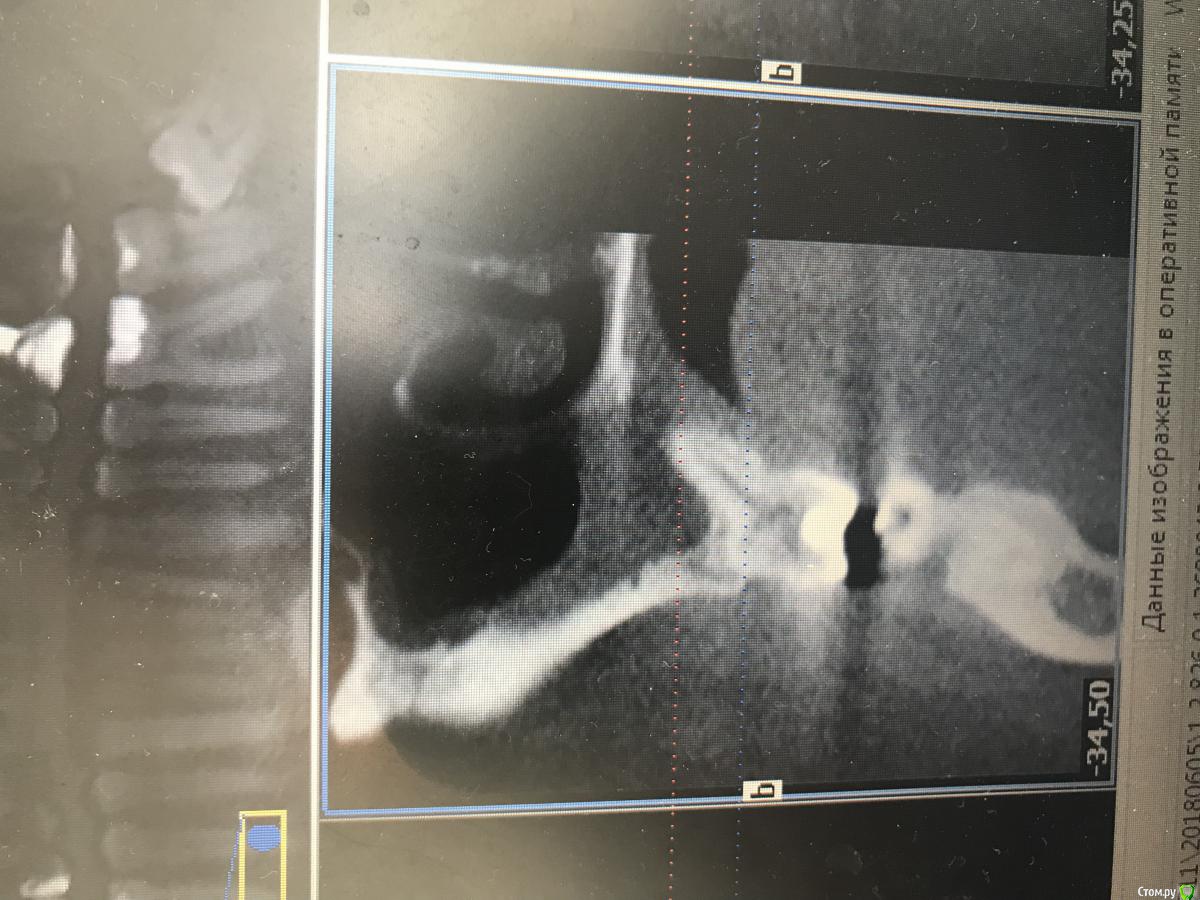

dr.Dre Опубликовано 6 июня, 2018 Поделиться Опубликовано 6 июня, 2018 (изменено) Добрый день ,коллеги такой клинический случай ,пациента нос заложен постоянно лор напривил сказал гайморит от зубов ,я думаю , что причина в 26 ,что скажите? Изменено 6 июня, 2018 пользователем dr.Dre Ссылка на комментарий

Дмитрий Л. Опубликовано 6 июня, 2018 Поделиться Опубликовано 6 июня, 2018 извините пожалуйста загрузил с телефона, у меня есть кт как можно загрузить на форум?Загрузить на файлообменник или облако (гугл диск, к примеру) и затем ссылку сюда. Я бы обратил внимание на 16. Но данных мало вы предоставили... гайморит... какой, 1-, 2-сторонний? Срезы непонятные Заложенность носа это ещё не гайморит. Жалобы на "зубы"? Перкуссия и т.д. Ссылка на комментарий

dr.Dre Опубликовано 6 июня, 2018 Автор Поделиться Опубликовано 6 июня, 2018 Загрузить на файлообменник или облако (гугл диск, к примеру) и затем ссылку сюда. Я бы обратил внимание на 16. Но данных мало вы предоставили... гайморит... какой, 1-, 2-сторонний? Срезы непонятные Заложенность носа это ещё не гайморит. Жалобы на "зубы"? Перкуссия и т.д.https://fex.net/714551533241 Ссылка на комментарий